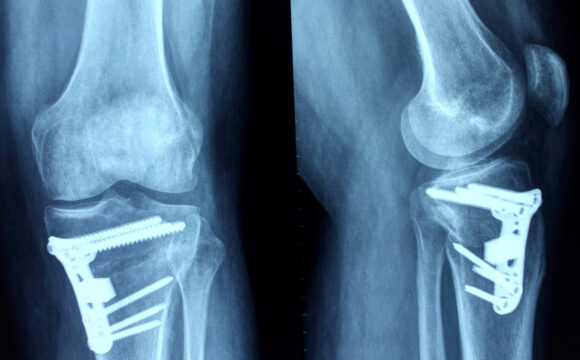

Utilizăm o varietate de metode avansate de diagnosticare, inclusiv radiografii, RMN-uri, tomografii computerizate și examinări fizice detaliate, pentru a identifica cu precizie afecțiunile și leziunile sistemului musculo-scheletic.

- Fracturi și luxații

- În cazurile severe, intervenții chirurgicale, cum ar fi artroscopia sau protezarea articulațiilor